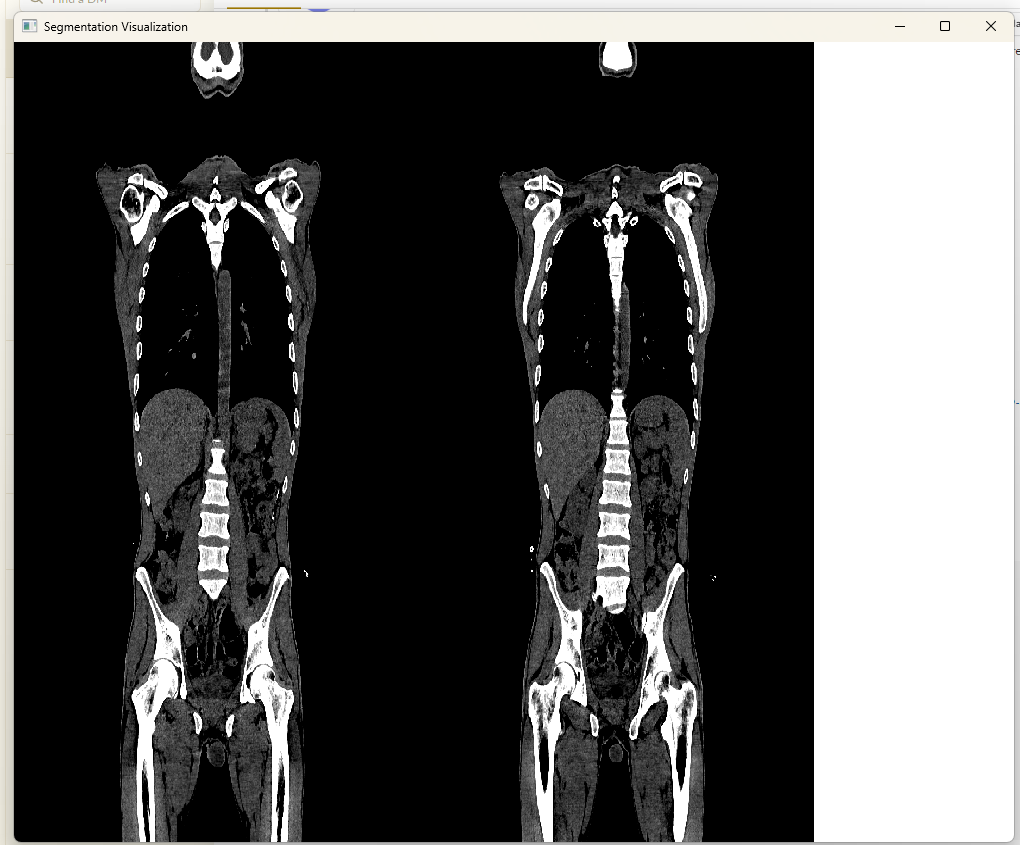

endAfter the integrity of the fragment shaders was verified in multi-image, voxel data for the images was integrated and further modifications to the high-level functions were made and eventually the following script produced a rather appealing result.

Script for loading the same NIFTI image twice in the visualizer for side-by-side display:

using MedEye3d

ctNiftiImage = "/home/hurtbadly/Downloads/ct_soft_study.nii.gz"

MedEye3d.SegmentationDisplay.displayImage([[ctNiftiImage],[ctNifitImage]])Results in :

Crosshair marker for image registration are displayed in the relevant passive image to hightlight the same anatomical regions based on the spatial meta-data of the images i.e spacing, origin and direction. In order to achive the crosshair rendering in the passive image, the following action items were devised:

Rendering of crosshair on OpenGL coordinate in passive image

Conversion between different coordinate systems and accounting for the image’s spatial metadata during calculating proved to be challenging at first, but with multiple revisions, a final solution was achieved with seemingly no noticeable amount of lag or delay. One such frame of [CT] images with crosshair display in multi-image is depicted below: